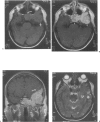

The authors present an unusual case of solitary intramedullary plasmacytoma. Awareness of this entity can facilitate appropriate surgical planning, which may include a limited biopsy prior to considering more extensive skull base surgery.